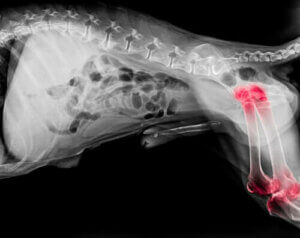

Eksperci uważają, że około jeden na pięć psów cierpi na zapalenie stawów. Chociaż ten stan może pojawić się w każdym wieku, występuje częściej u starszych psów. Ogólnie rzecz biorąc, zapalenie stawów jest chorobą zwyrodnieniową, która powoduje zapalenie stawów łokciowych i barkowych.